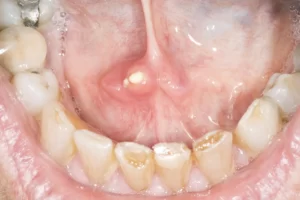

Symptoms of sialolithasis may include:sialolithasis

• A painful lump in the affected gland, with pain worsening during eating.

• A tender, painful lump in the cheek or under the chin.

• A foul-tasting discharge of pus from the duct into the mouth

• A lump or palpable stone on the floor of the mouth